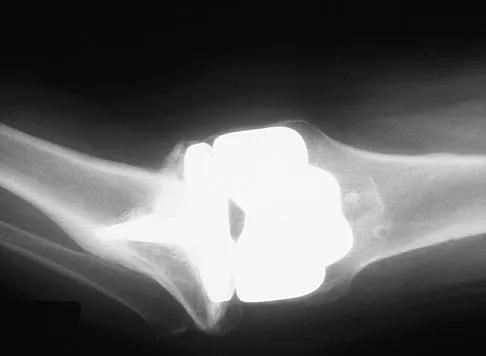

A 15-year-old boy falls from his bicycle and sustains an injury to his elbow. Prereduction radiographs are shown in Figure 12a. Closed reduction is performed without difficulty and postreduction radiographs are shown in Figure 12b. What is the next most appropriate step in treatment?

Explanation

Elbow dislocations in children are rare injuries and usually result from a fall on an outstretched arm. The incidence of these injuries increases as patients age and concurrently the incidence of supracondylar humerus fractures decreases. In adolescent patients, simple elbow dislocations are treated with splint immobilization and the initiation of physical therapy once comfortable. The practitioner must be aware of structures that may get caught in the joint on reduction. These include the median nerve as well as the medial epicondyle. In this patient, the radiographs reveal a medial epicondyle fracture. Postreduction radiographs show the joint to be incongruous secondary to intra-articular displacement. At this point, the most appropriate treatment is to perform an open reduction and repair of the medial epicondyle fragment. Rasool MN: Dislocations of the elbow in children. J Bone Joint Surg Br 2004;86:1050-1058.